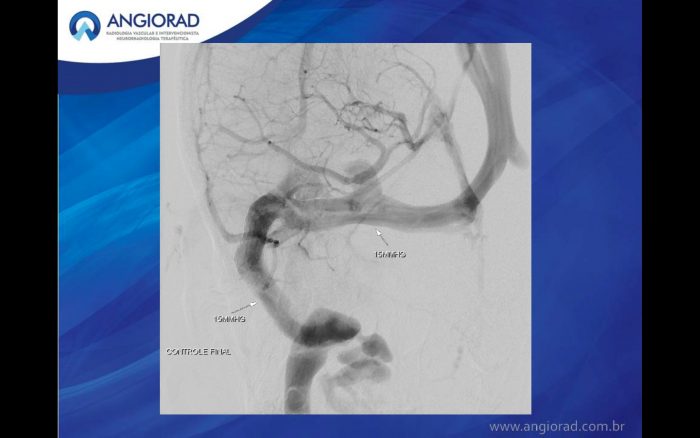

O caso ilustrado é de uma paciente de 33 anos com papiledema, cefaleia intensa, zumbido e perda progressiva do campo visual. Foram realizadas aferioções da pressão em todo trajeto do seio transverso e sigmoide direito, sendo evidenciado diferença de pressão de 10 mm/Hg relacionada ao ponto de estenose. Após o diagnóstico, foi instituído o tratamento por angioplastia com Stent (Precise – Cordis), devido sua facilidade de navegação e acomodação em tortuosidades. O procedimento transcorreu sem intercorrências, havendo resolução completa dos sintomas após 30 dias.